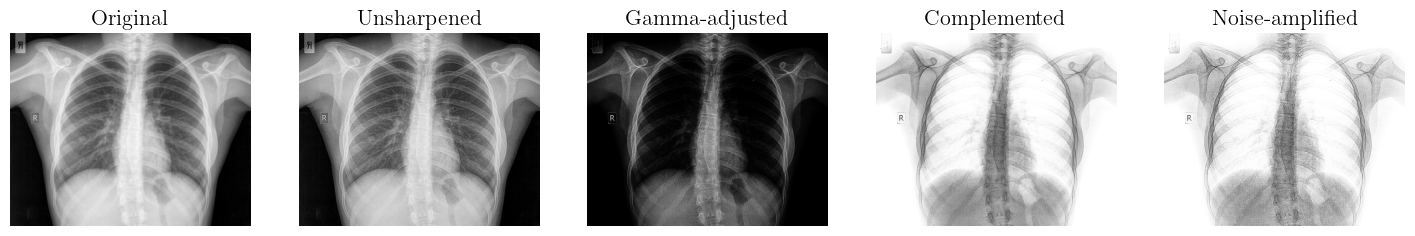

We applied a bidirectional pipeline designed to transform images between two visual states, such as from (image_1) to (image_2) and vice versa, using spatial enhancement techniques. This process involves applying image processing operations like filtering, sharpening, histogram equalization, or edge enhancement to modify spatial features such as contrast, texture, and detail [42]. In the forward direction (image_1 to image_2), enhancements might emphasize features like edges or brightness to highlight specific content. The reverse transformation (image_2 to image_1) uses inverse or compensatory techniques to restore the original spatial characteristics. Key to this bidirectional process is the preservation of structural information, allowing for meaningful reversibility. Adaptive methods may be employed to ensure transformations remain context-aware and minimize loss of detail or introduction of artifacts [43].

The forward pipeline (Image 1 to Image 2) comprises spatial enhancement techniques such as histogram equalization, sharpening, and contrast stretching. These operations are applied sequentially to improve image detail, enhance edges, and increase dynamic range, transforming (image_1) into a visually enhanced version (image_2) while preserving essential structural and contextual features. However, we applied unsharp masking, a technique that enhances edges by subtracting a blurred version of the image from the original. A kernel combines two filters: a low-pass filter (typically a Gaussian blur) to smooth the image and a high-pass filter to extract edge details. The final image is produced by adding a scaled version of the high-pass result back to the original image [44]. This enhances fine structures and sharpens transitions without significantly amplifying noise. The combined kernel thus balances detail enhancement and noise suppression, making unsharp masking effective for improving visual clarity in both natural and synthetic images [45].

Noise Amplification: Subtracts a Gaussian-blurred image (7 x 7 kernel) to isolate noise, multiplies by β[1.6,2.1]\beta\in[1.6,2.1], and adds back to the image. Parameters are optimized using a blended SSIM+NMI metric, achieving 76.10% similarity.

Figure 1: Proposed bidirectional image-to-image transformation pipeline. An adaptive SSIM+NMI module tunes parameters to ensure reversibility, minimize artifacts, and highlight scientific novelty in reversible spatial enhancement.

fine-tuning to reverse nonlinear intensity shifts. Despite these efforts, the reverse transformation achieves a maximum of 74.80% similarity, primarily due to irreversible information loss from noise amplification and detail suppression during the forward enhancement. A comparative analysis of the two images reveals that (image_2) is the complement of (image_1). Moreover, (image_2) exhibits increased noise levels, as well as differences in dynamic range and brightness relative to image_1. To generate (image_2) from (image_1), a spatial enhancement pipeline comprising several stages is employed. The pipeline includes the following operations:

This pipeline successfully synthesizes image_2 from image_1 while accommodating variations in noise, brightness, and dynamic range. Parameter optimization for each stage was conducted using the optimal_parameters() function, albeit via a heuristic approach.

The quantitative evaluation of the proposed transformation pipeline was conducted using a blended similarity index that combines the Structural Similarity Index (SSIM) and the Normalized Mutual Information (NMI). This hybrid metric jointly captures perceptual fidelity and information preservation, thereby providing a more comprehensive assessment of transformation consistency. For the forward pipeline (image_1 \rightarrow image_2), the framework achieved a blended SSIM+NMI score of 76.10%. This relatively high score indicates that sequential operations—including unsharp masking for detail enhancement, gamma correction for perceptual brightness balancing, intensity complementation, and controlled noise amplification—were effective in generating visually consistent and structurally reliable outputs. The preservation of edge sharpness and global luminance distribution underscores the robustness of the forward transformation process.

In contrast, the reverse pipeline (image_2 \rightarrow image_1) achieved a score of 74.80%. The slight reduction reflects cumulative information loss introduced by noise amplification and nonlinear intensity mappings, which hinder perfect reversibility. Despite this, the reverse transformation still demonstrates acceptable fidelity, suggesting that essential structural and statistical properties of the original image are largely preserved. These results highlight the forward pipeline’s efficiency for enhancement tasks while emphasizing the inherent challenges of fully reconstructive inverse transformations in noisy imaging environments.